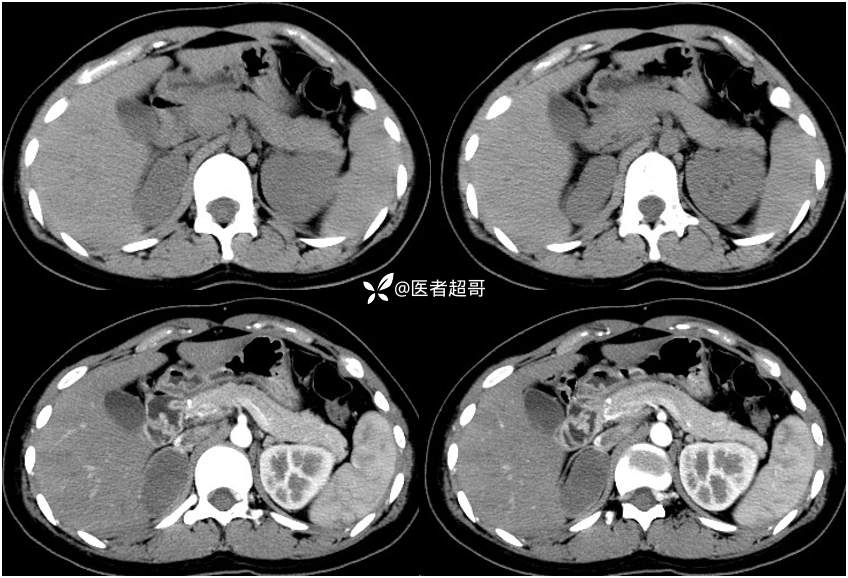

病例【影诊笔记712】女,32岁,体检发现右侧肾上腺占位1年,有病理结果!